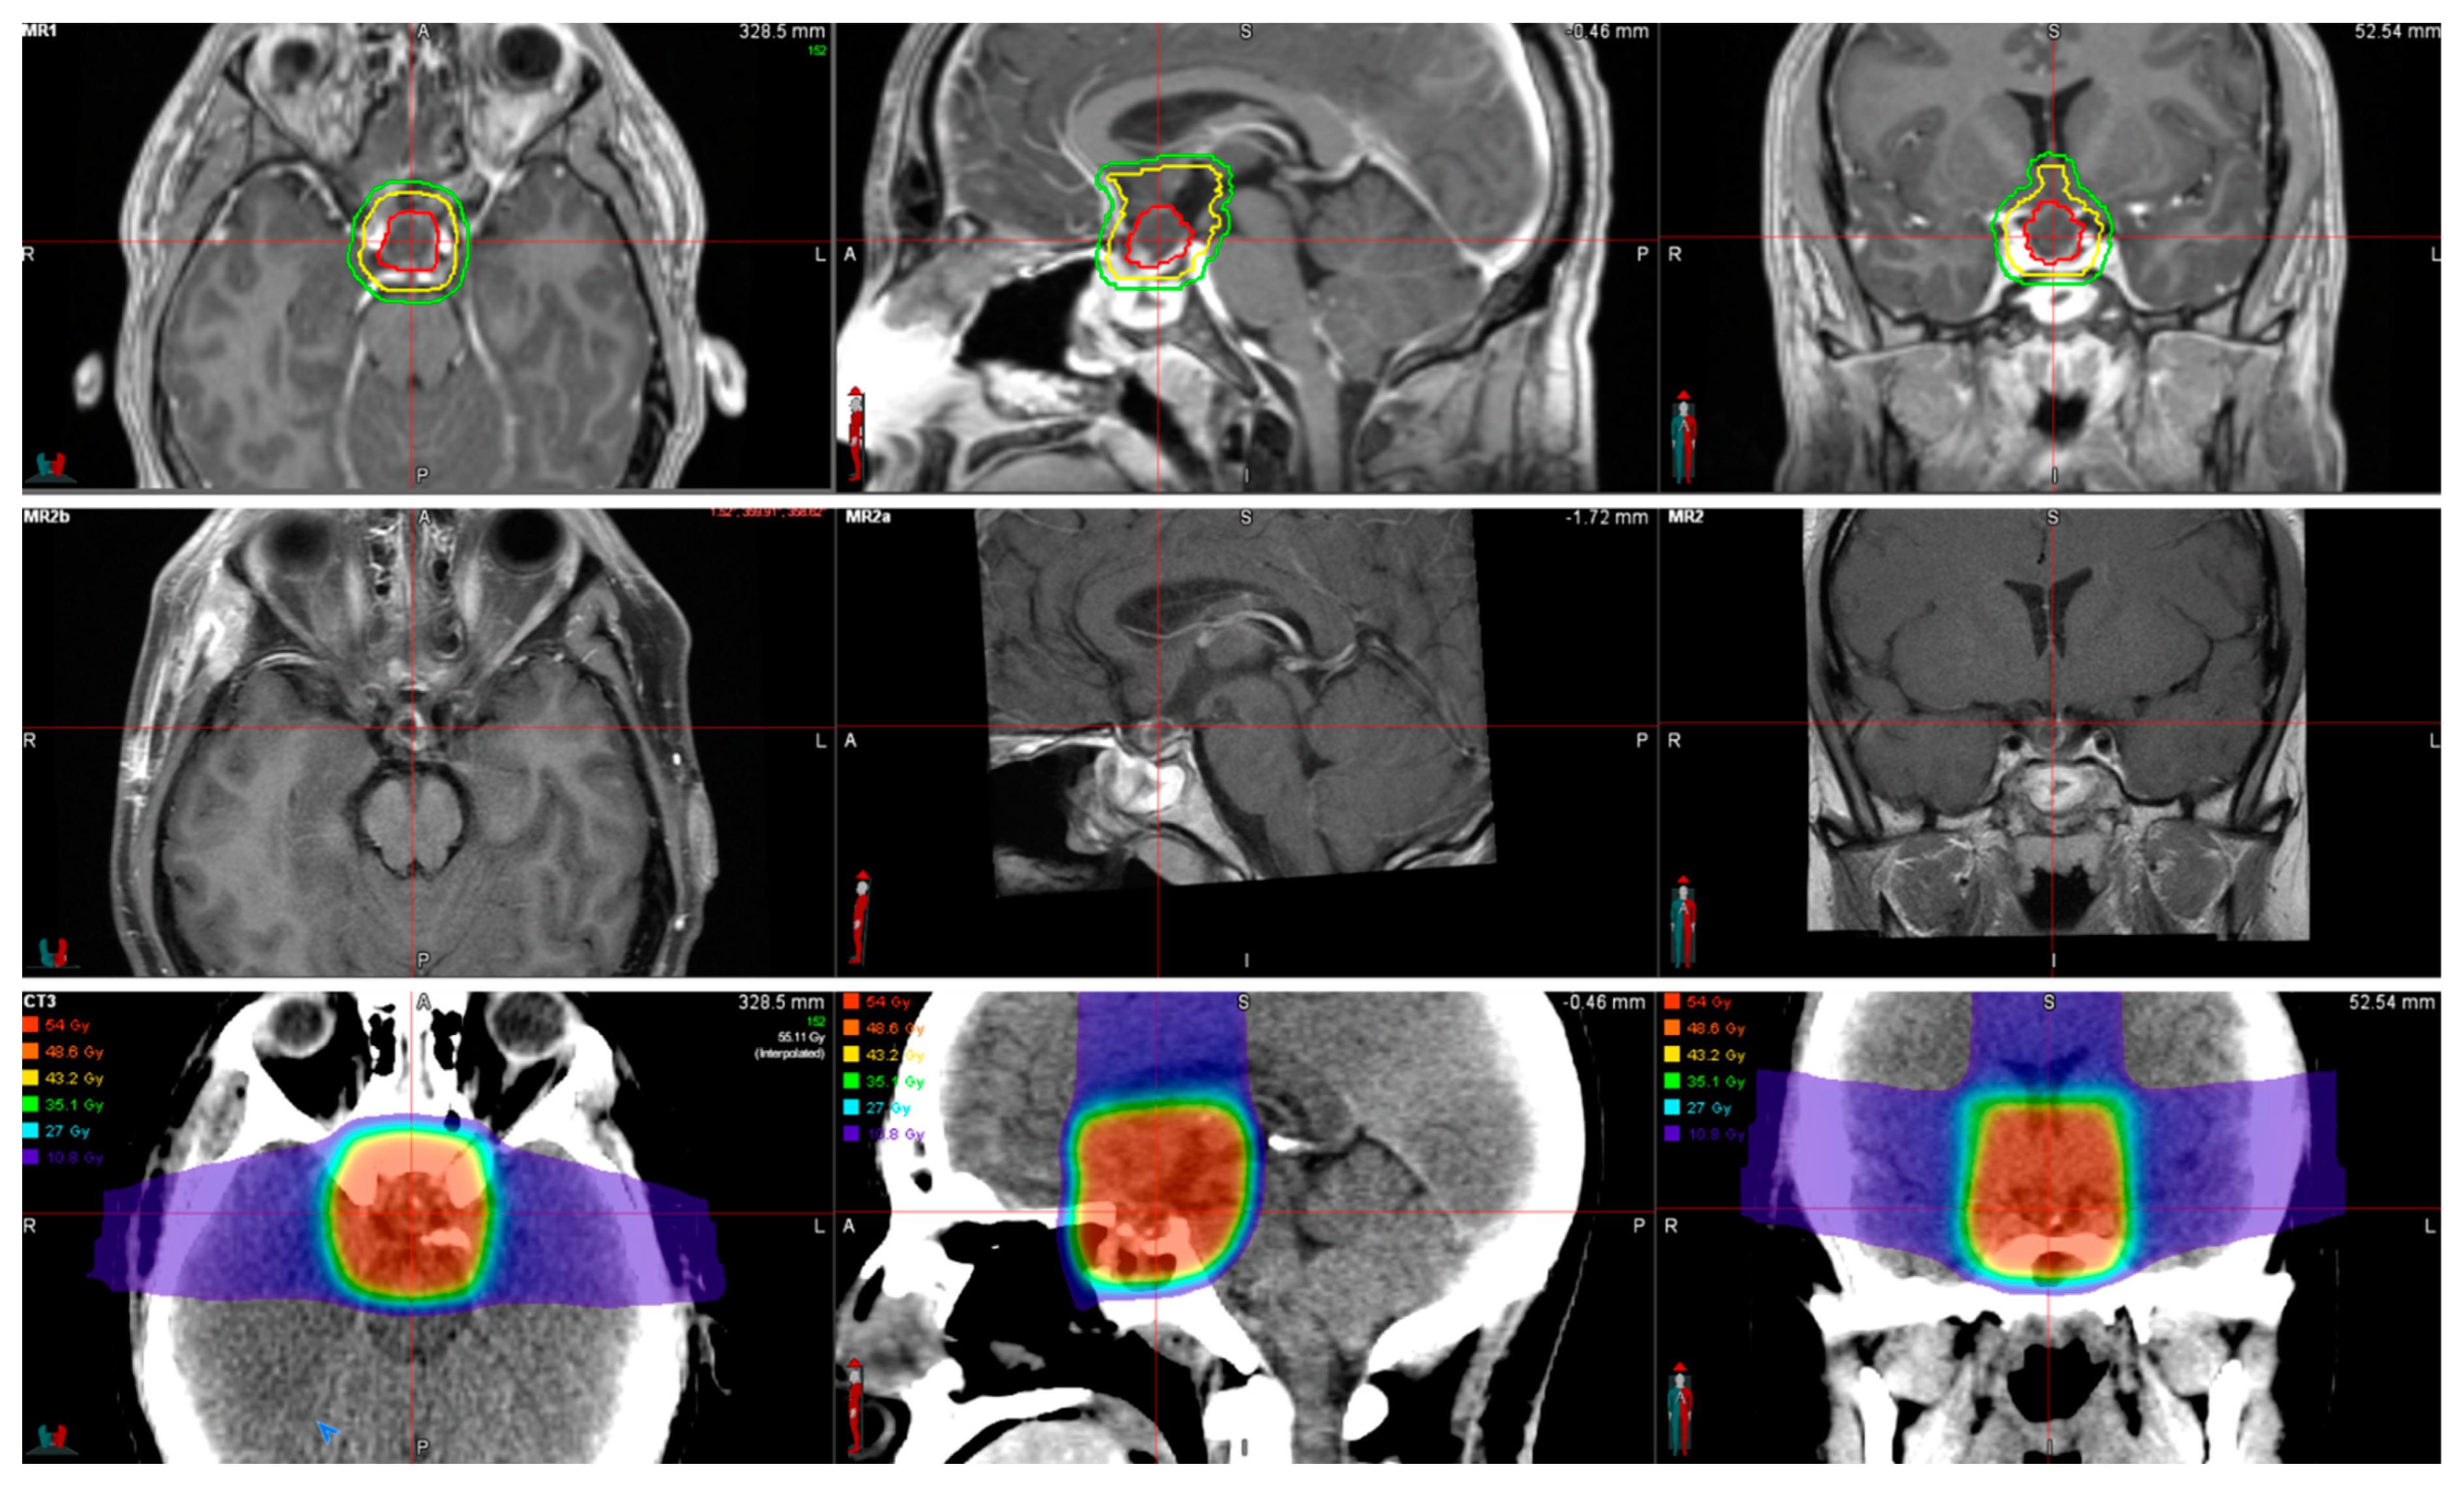

小児神経の画像診断 改訂第2版: ―脳脊髄から頭頸部・骨軟部まで。Neuroimaging Findings in a Patient with Anti-IgLON5 Disease。Topography and Radiological Variables as Ancillary。「小児神経の画像診断 = Diagnostic Imaging of Infantile Neurologic Diseases : 脳脊髄から頭頸部・骨軟部まで」大場 洋 / 大場 洋 / 髙梨 潤一 / 髙梨 潤一 / 森 墾 / 森 墾定価: ¥ 15000裁断しています。タイ方医学知識と理論。#大場洋 #大場_洋 #大場洋 #大場_洋 #髙梨潤一 #髙梨_潤一 #髙梨潤一 #髙梨_潤一 #森墾 #森_墾 #森墾 #森_墾 #本 #自然/医療・薬学・健康。健康教育マニュアル。書き込み等はありません。ページも全て揃ってページ順となってます。病理解剖実践ガイドブック 2025